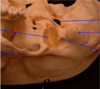

A- Cribiform plate of the ethmoid bone B - optic canal of the sphenoid bone C - internal acoustic meatus D - hypoglossal canal of the occipital bone E - jugular foramen petrous region temp F - Foramen spinosum G - Foramen Ovale H-Foramen rotundum.

A - Foramen Spinosum B - Foramen Ovale C - Carotid Canal D - Cribiform plate E - Foramen Lacerum F - Carotid canal G - Foramen Magnum of the occipital bone H - Internal acoustic meatus.